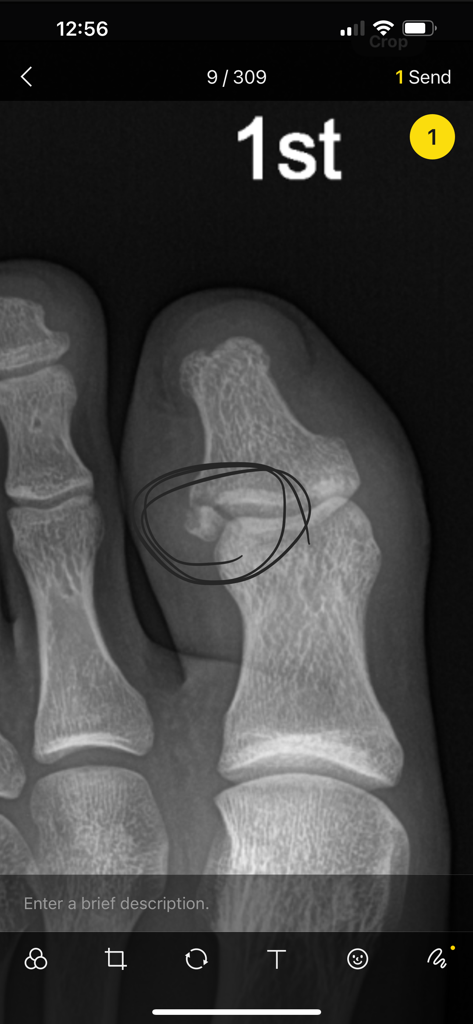

첫번째 사진이 12월11일날 찍은 엑스레이이고, 저 후에 보존적 치료 권하여 깁스를 했습니다. 붓기가 매우 심하여 2주뒤에 오 라하셔서 2주뒤에 내원했습니다. 2주뒤인 15일에도 붓기가 심한 상태입니다. 통증도 있고

그리고 15일 후인 12월26일인 날에 가서 다시 엑스레이를 찍었 는데

이렇게 원위지골의 전위가 발생하여 불유합 가능성이 높다고 진 단을 받았습니다. 저렇게 뼈가 조각나서 전위가 발생했네요.

1) 혹시 수술적 치료를 하면 핀을 박는 수술을 하나요? 아니면 저 조각난 뼈를 제거하는 수술을 하나요?

2) 저정도 크기의 뼈조각이면 핀으로 고정할 수 있는 정도인가 요?

고정하기엔 크기가 너무 작아서 제거하는걸 고려해볼수 있을것 같습니다.